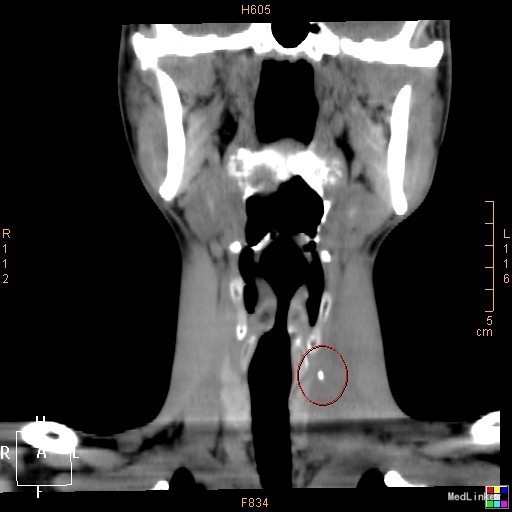

该患者在诊断上是有些困难,颈部多发脓肿是明确的,但是瘘口的位置不好确定,从而未能确诊,8年前患者行上消化道钡餐检查,诊断“食管瘘”,但是我们从8年前的影像上看,瘘口的位置太高,不像是食管的瘘口,考虑是不是梨状窝的瘘道,为了进一步确诊,我们给患者行了胃镜检查,结果胃镜发现左侧梨状窝有1个3mm大小的小孔,胃镜未能通过,食管未见明显的瘘口。为了更加明确瘘口的位置,我们与影像科商议后决定口服造影剂后行颈部CT平扫,因怕钡餐沉积在脓肿内不好排出,我们采用了口服碘化油。此次影像明确了瘘口的确在左侧梨状窝。最终诊断:左侧颈部多发脓肿;左侧梨状窝瘘道形成。 治疗:入院后予抗感染、禁食、营养支持等治疗,患者感染得以控制,请耳鼻咽喉科会诊后建议转科治疗。